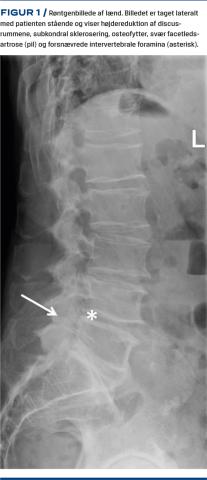

Ved røntgenoptagelse af bækkenet/SI-led kan man påvise sværere grader af artrose i form af osteofytter, sklerosering og ledspalteafsmalning. Pga. leddets lejring er undersøgelsen ikke sensitiv for lettere forandringer. Ved CT påvises der fokal irregulær ledspalteafsmalning, marginale osteofytter, subkondral sklerosering, cystedannelse og vakuumfænomener (Figur 3). Der observeres samme grad af artrose hos patienter med kroniske SI-ledsmerter og raske kontrolpersoner, og CT er ikke valideret til identifikation af symptomatisk SI-ledsartrose [21]. Ved MR-skanning kan man ligesom ved CT påvise uregelmæssig ledspalteafsmalning, osteofytter og forskellige grader af sklerosering [22]. Subkondral eller periartikulær knoglemarvsødem er et hyppigt fund hos patienter, der har kroniske uspecifikke rygsmerter på degenerativ basis [23]. Degenerative forandringer ses hos både aymptomatiske patienter og patienter med kroniske rygsmerter og kan ikke stå alene uden en klinisk vurdering.